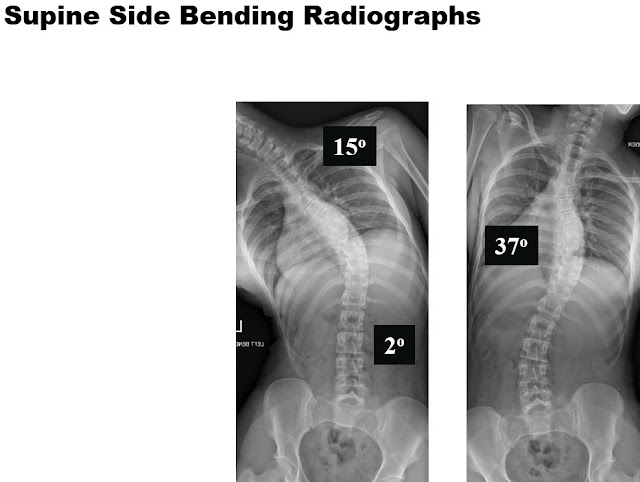

The supine side bending radiographs demonstrate the flexibility of the spine. So only the main thoracic curve of 58 degrees is what we call “structural” and the other two curves, due to the fact they bend out to be below 25 degrees, we call “nonstructural” or “compensatory”.